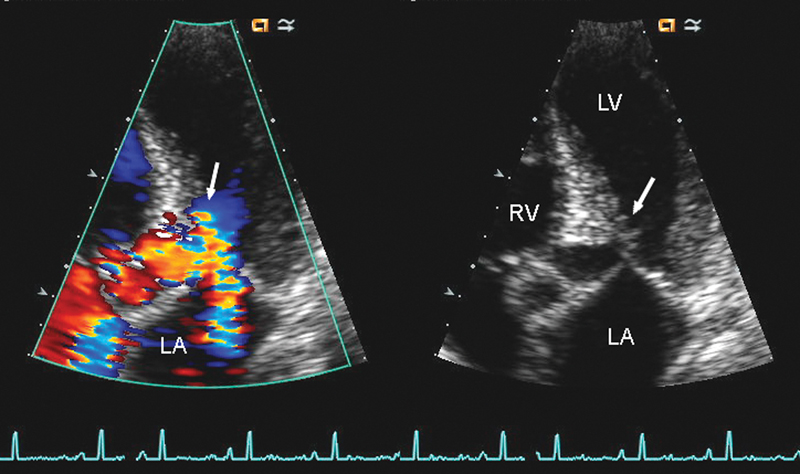

فحوصات تشخيصية لبعض امراض القلب والشرايين التاجية